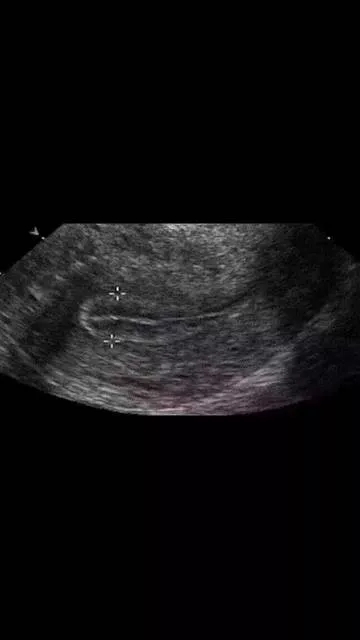

在平时进行内膜检测过程中,医生?;崴档侥谀ぬ ⑻?、不均质、有强光团,或内膜形态不好、三线不清、内膜线中断等等。

以上这些情况不利于胚胎着床和发育,不适宜移植新鲜胚胎,建议做一下宫腔镜检查,排除子宫内膜息肉、宫腔粘连、慢性子宫内膜炎症、内膜过度增生,以及双角子宫、单角子宫、子宫纵膈等等的病变,并进行相应的治疗。等内膜的病变去除,宫腔形态恢复以后再予以移植为好。